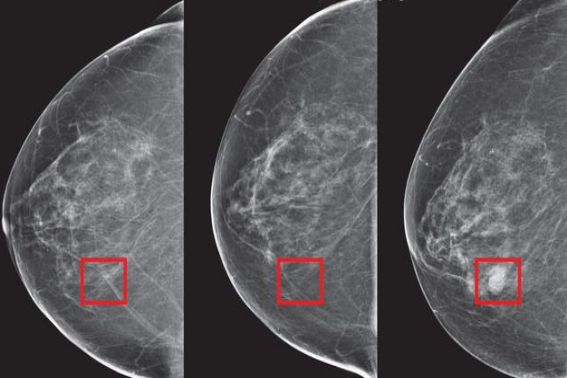

经过医生的诊断和检查结果显示 , 小李的双侧腋窝下均长了5、6个0.3cm的结节 , 左侧乳房上的结节最大有1.2cm 。 听到结果后她呆了 , 她只是听过这个病 , 但是没有想过自己竟然会患上这个病 , 于是她立马向医生询问到 。